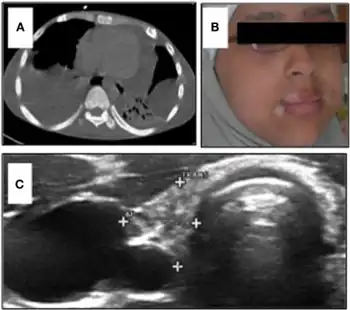

LRBA deficiency presents as a syndrome of autoimmunity, lymphoproliferation, and humoral immune deficiency. Predominant clinical problems include idiopathic thrombocytopenic purpura (ITP), autoimmune hemolytic anemia (AIHA), and an autoimmune enteropathy.[1] Before the discovery of these gene mutations, patients were diagnosed with common variable immune deficiency (CVID), which is characterized by low antibody levels and recurrent infections. Infections mostly affect the respiratory tract, as many patients suffer from chronic lung disease, pneumonias, and bronchiectasis. Lymphocytic interstitial lung disease (ILD) is also observed, which complicates breathing and leads to impairment of lung function and mortality.[2] Infections can also occur at other sites, such as the eyes, skin and gastrointestinal tract. Many patients suffer from chronic diarrhea and inflammatory bowel disease. Other clinical features can include hepatosplenomegaly, reoccurring warts, growth retardation, allergic dermatitis, and arthritis.[1] Notably, LRBA deficiency has also been associated with type 1 diabetes mellitus.[2] There is significant clinical phenotypic overlap with disease caused by CTLA4 haploinsufficiency. Since LRBA loss results in a loss of CTLA4 protein, the immune dysregulation syndrome of LRBA deficient patients can be attributed to the secondary loss of CTLA4. Because the predominant features of the disease include autoantibody-mediated disease (AIHA, ITP), Treg defects (resembling those found in CTLA4 haploinsufficient patients), autoimmune infiltration (of non-lymphoid organs, also resembling that found in CTLA4 haploinsufficient patients), and enteropathy, the disease has been termed LATAIE for LRBA deficiency with autoantibodies, Treg defects, autoimmune infiltration, and enteropathy.